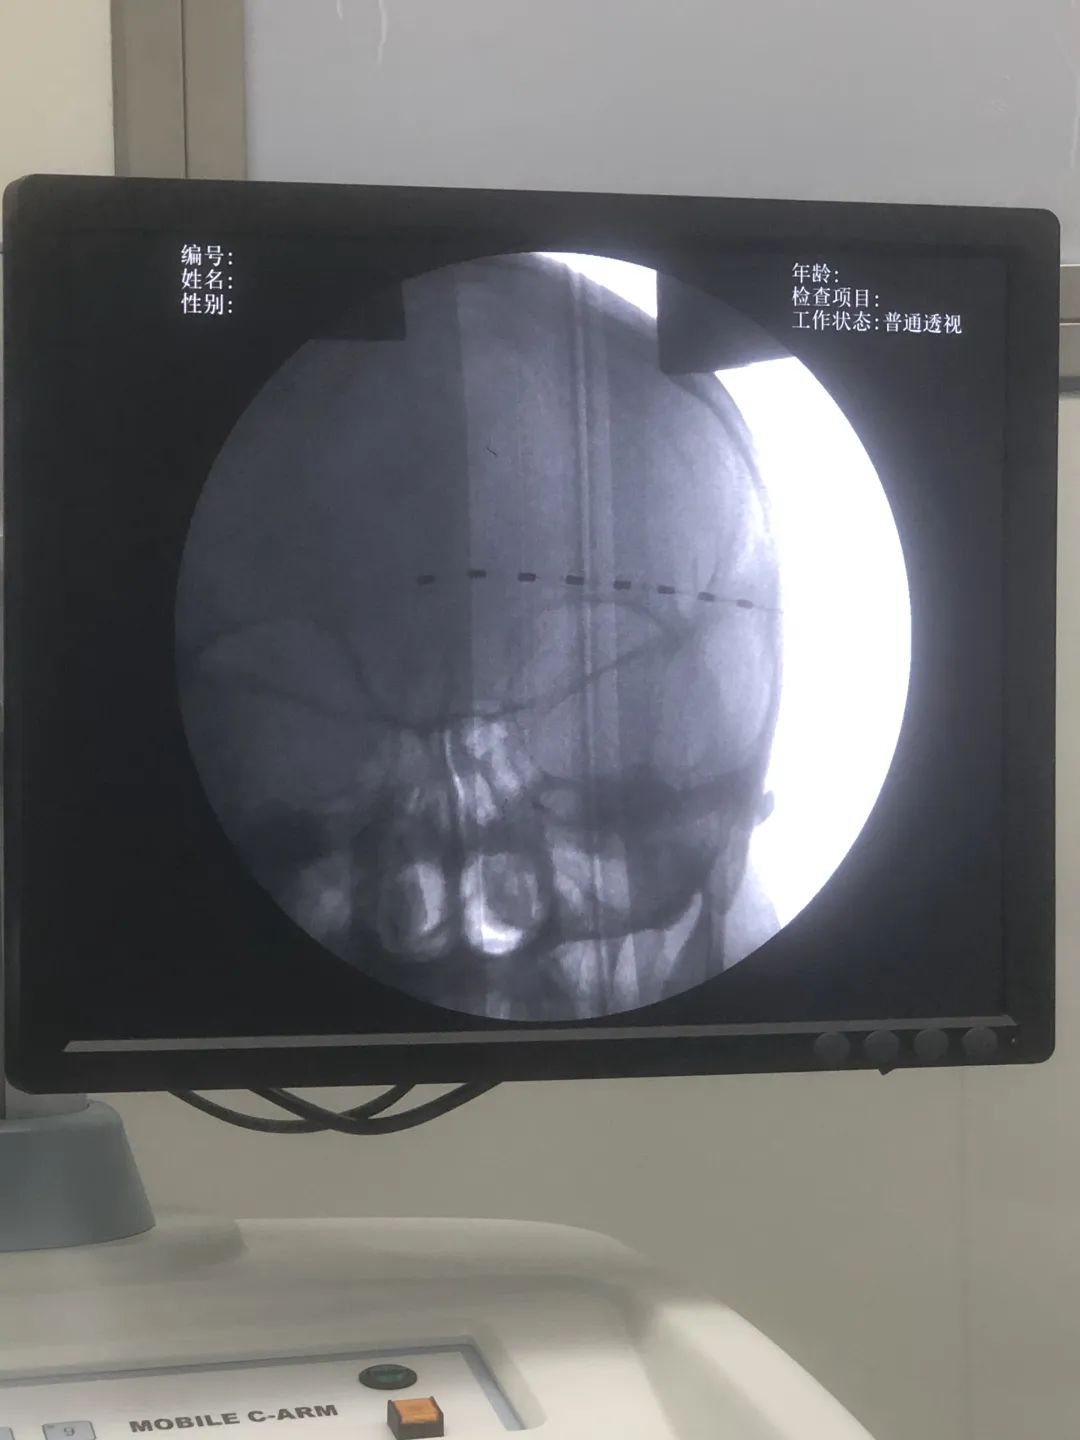

考虑到患者目前射频热凝术后疼痛控制不佳,且严重影响生活质量,经过科室严格讨论后,确定患者有神经电刺激植入术的适应症,家属同意该治疗方案。术中在超声及C臂联合定位下,顺利植入电极,电刺激测试完全覆盖疼痛区域。今日查房,患者疼痛评分降至2-3分,夜间睡眠良好。